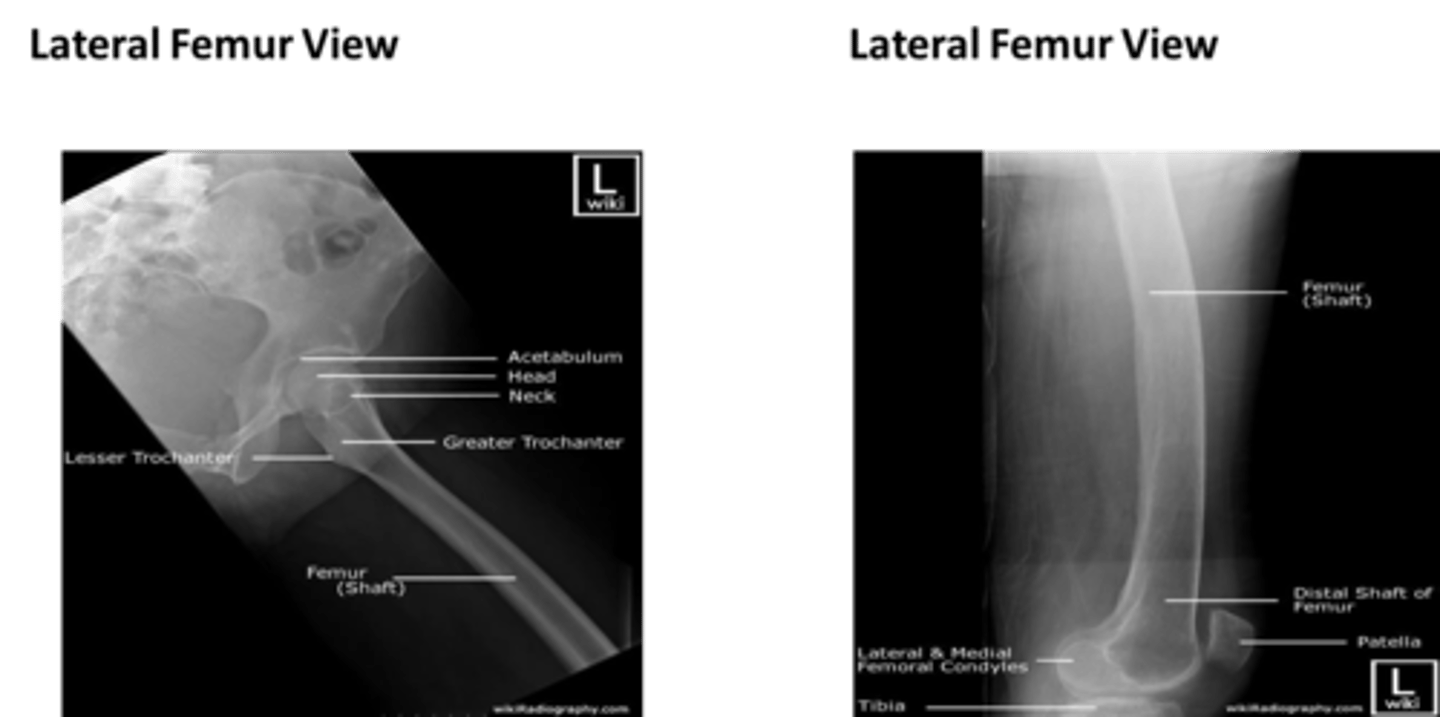

What are the main basic projections for imaging of the FEMUR?

- Antero-posterior (AP)

- Lateral

Describe, in detail, how we should position the PATIENT when doing a LATERAL FEMUR projection.

1. Patient is turned onto the affected side, lateral aspect of the leg in contact with the IR.

2. Femur oriented diagonally across an IR if 'out of bucky'.

3. Knee joint flexed and condyles should be superimposed.

4. Pelvis rotated backwards to separate the thighs.

5. Hip down image on second IR in bucky (if not possible to get both joints on one IR)

How should we position the X-RAY TUBE when doing a LATERAL FEMUR projection?

SID

Central ray

Centring point

SID: 110 - 115cm

Central ray: 90 degrees to the IR

Centring point: midline of the thigh; midway between the hip & knee joint.

How should we COLLIMATE when doing a LATERAL FEMUR projection? What structures should be included in the image?

- to include the entire length of the femur and lateral soft tissue borders. The knee and hip joint must also be included.